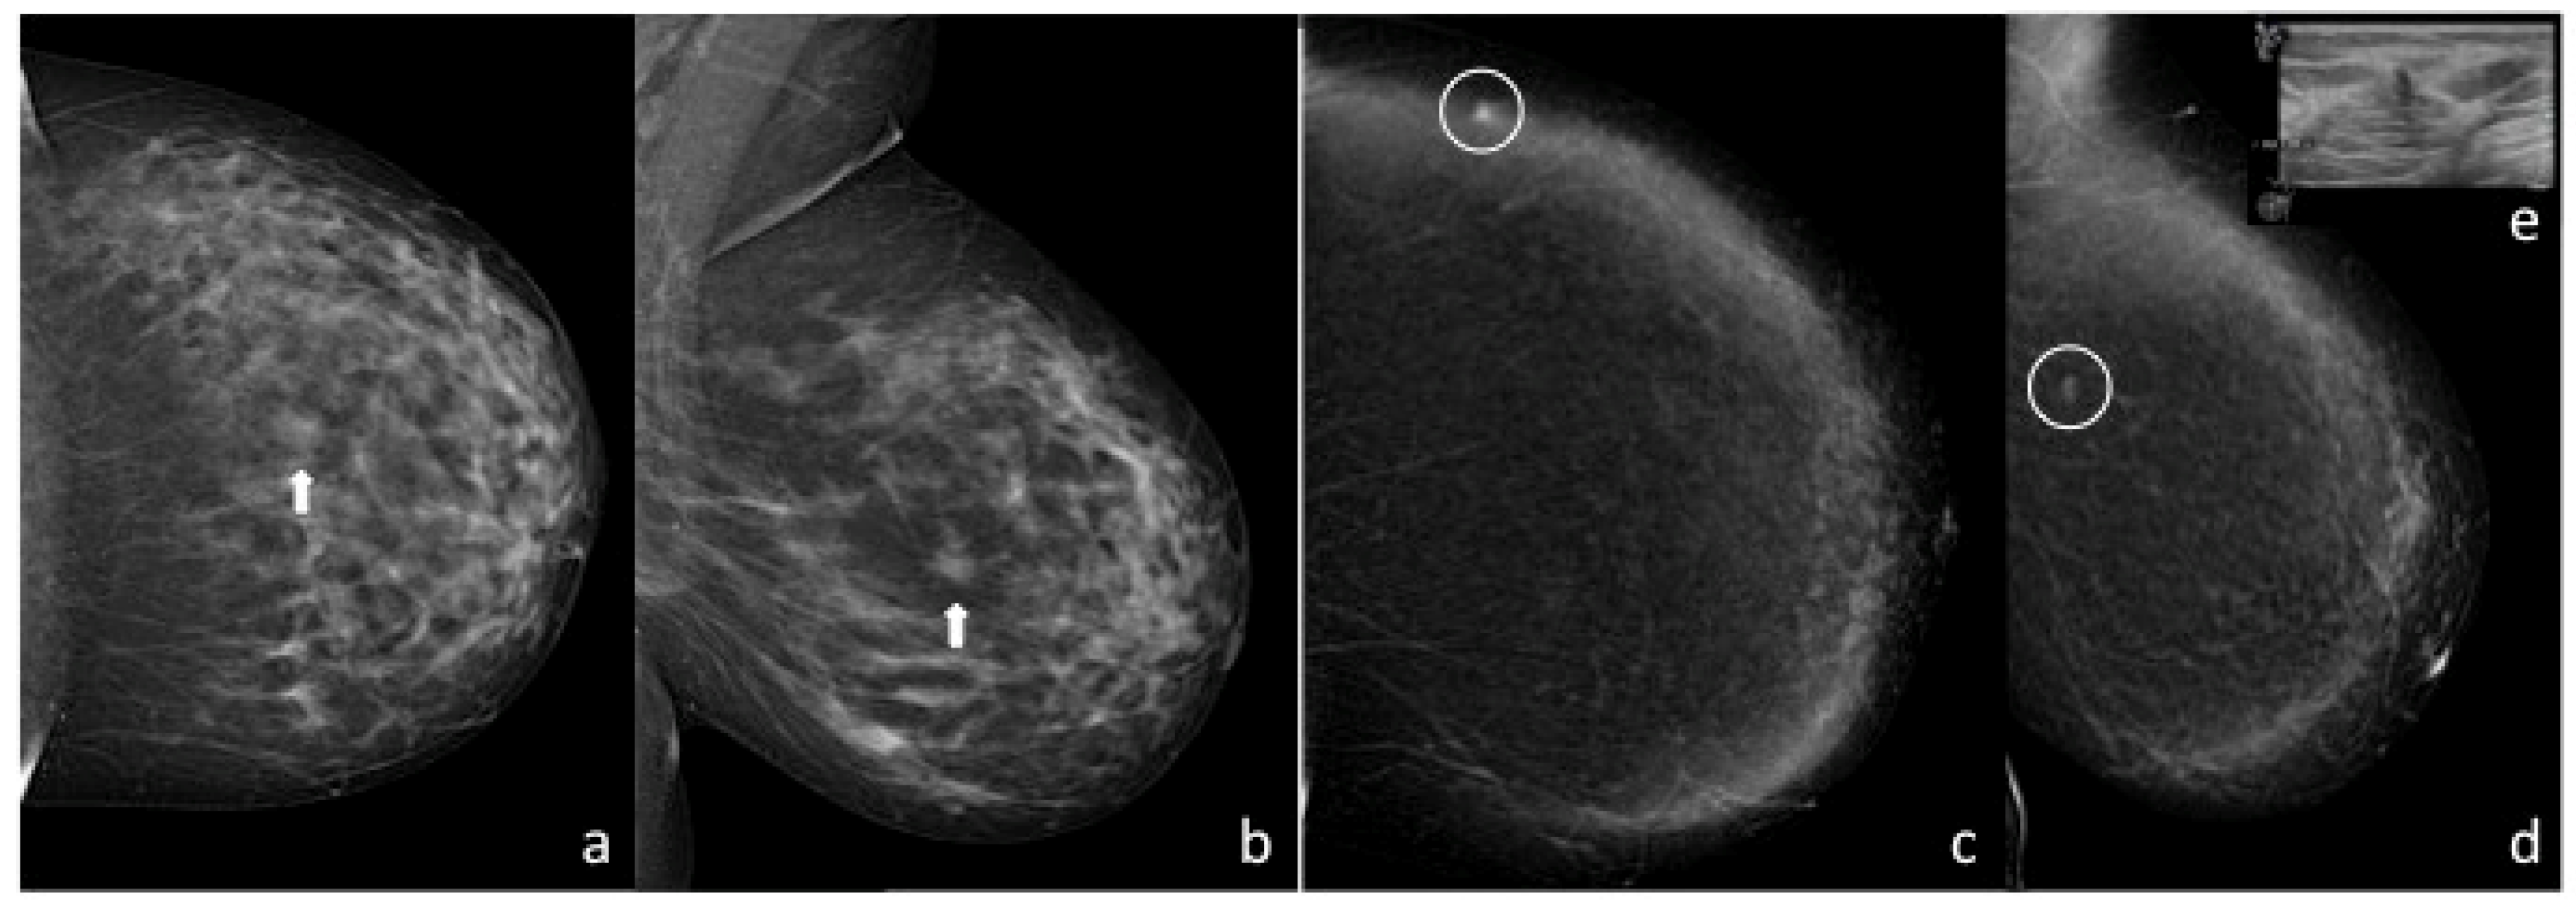

2. Materials and Methods

2.2. Imaging Techniques

2.3. Imaging Evaluation and Interpretation